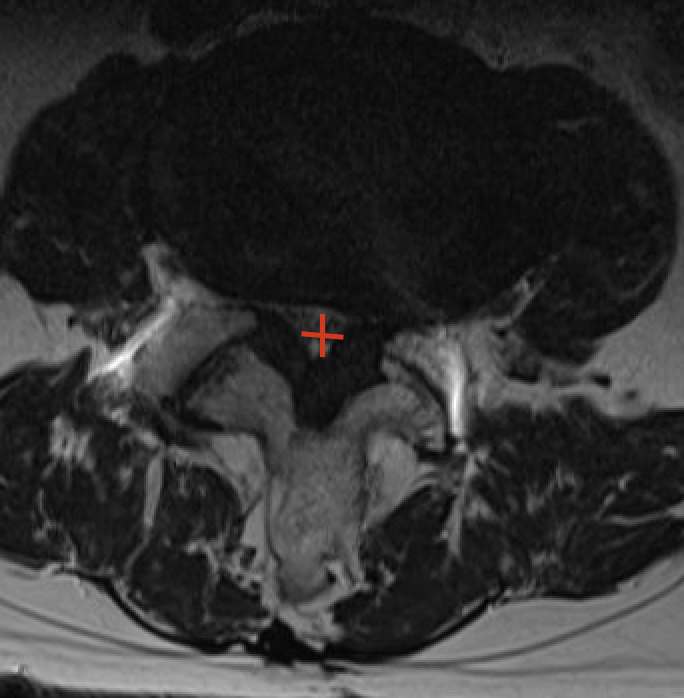

De diagnose wordt het best gesteld door middel van een NMR (=MRI) van de lumbale wervelkolom. Wanneer deze niet mogelijk is door claustrofobie of de aanwezigheid van pacemaker of neurostimulator, is een CT scan van de lage rug een goed alternatief. Bijkomend kan een EMG van de onderste ledematen het zenuwlijden bevestigen. Dit zenuwonderzoek wordt uitgevoerd door een neuroloog of fysisch geneesheer.

Hemilaminectomie is de behandeling van spinaalkanaalstenose op oudere leeftijd. Het doel van de ingreep is om het ruggenmerg terug voldoende plaats te geven. Spinaalkanaalstenose is immers een slijtagefenomeen waarbij het ruggenmergkanaal progressief wordt afgekneld door uitpuiling van de tussenwervelschijf, beenderige aanwassen ter hoogte van de achterste gewrichten en een verdikking van het ligament tussen de wervelbogen. Dit veroorzaakt pijn ter hoogte van de onderste ledematen en een progressieve achteruitgang van het staan en stappen.

Spinaalkanaalstenose is een vernauwing van het ruggenmergkanaal welke centraal of perifeer kan zijn. Deze vernauwing wordt veroorzaakt door een uitpuiling van de discus naar achter toe, beenderige aanwassen aan de achterzijde van het wervellichaam, verdikking van het ligamentum flavum (ligament dat de ene wervelboog met de andere verbindt) en het groter worden van de facetgewrichten (door artrose: klassieke beeld vernauwing en verbreding van het gewricht). Deze vernauwing veroorzaakt een belangrijke druk op het ruggenmerg (=centrale stenose) en/of zenuwen (=perifere stenose) waardoor belangrijke pijn in 1 of beide benen kan ontstaan.